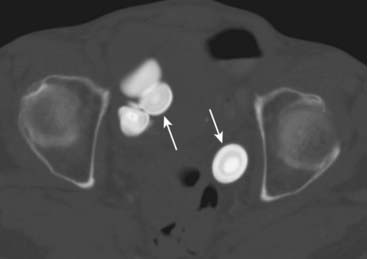

image

Figure 16-10 Urinary bladder stones.

There are laminated calcifications (solid white arrows) seen on this axial CT scan through the level of the pelvis and windowed to show the laminations better. The laminations imply that these calcifications have formed inside of a hollow viscus. The anatomic location of these calculi places them in the urinary bladder.